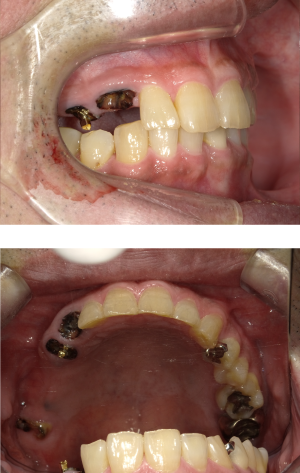

30代 女性 インプラント治療(鎮静療法)

| 年代・性別 | 30代・女性 |

|---|---|

| 主訴 | 口腔内かなり状態悪く、これから先しっかり噛んで食事ができるようにインプラントを入れたい。 |

| 部位 | 左上3,5,7、右下5 |

| 治療期間 | 約11ヶ月 |

| 費用 | ¥2,145,000(税込) |

| 副作用・リスク |

|